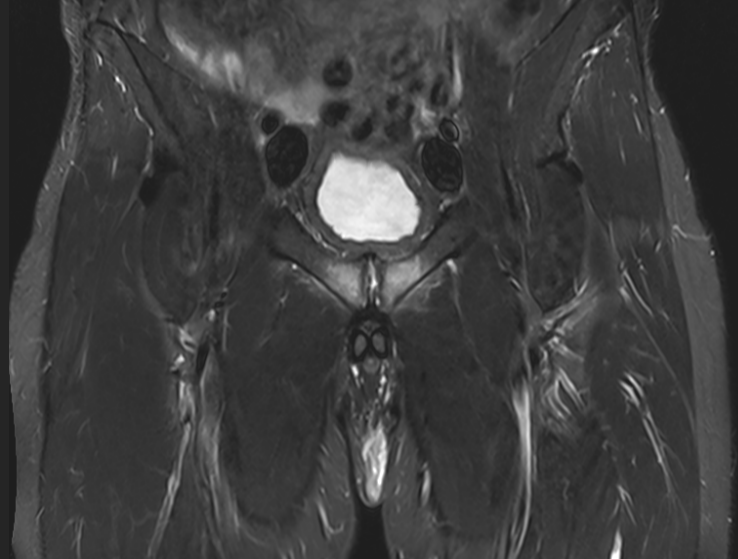

3. Osteitis pubis